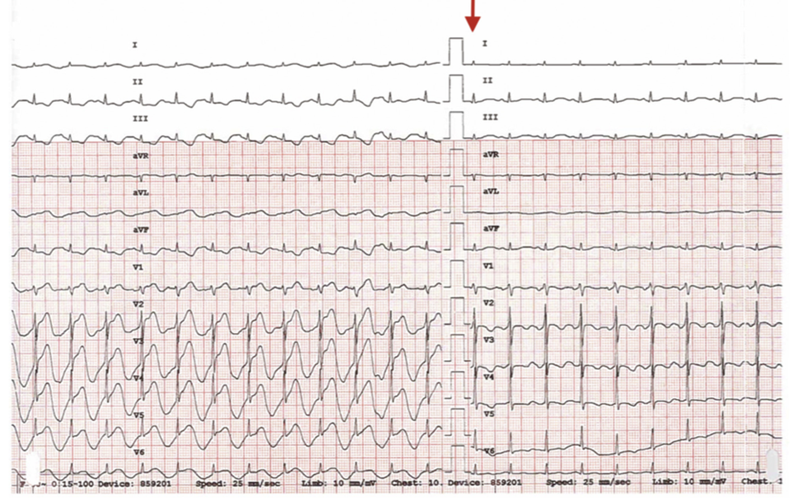

随后在上腹部按压或松手下行12导联心电图,也清楚地重现了这一动态

图片尺寸793x500

患者男性,55岁,反复发作心前区疼痛2年,2周前查心电图示左室面导联st

图片尺寸596x320